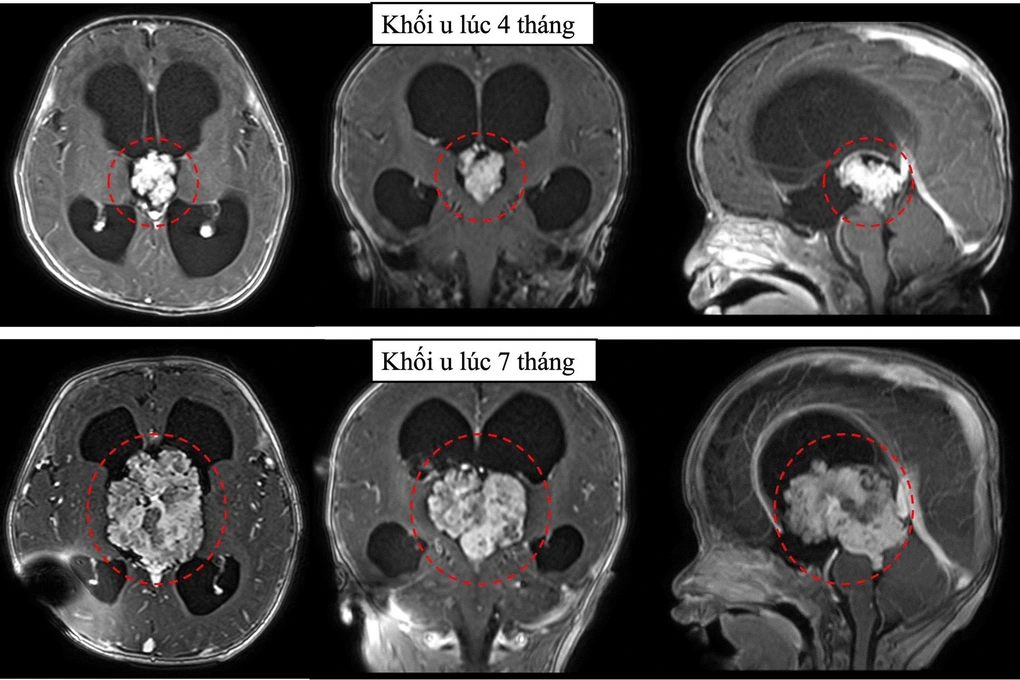

Nhưng 3 tháng sau, khi chụp phim cộng hưởng từ sọ não, bác sĩ phát hiện khối u tăng kích thước hơn gấp 3 lần. Không thể trì hoãn thêm, ê-kíp điều trị tư vấn gia đình việc phẫu thuật mổ lấy u để cấp cứu cháu bé.

Khối u tăng kích thước gấp 3 lần trong thời gian ngắn (Ảnh: BV).